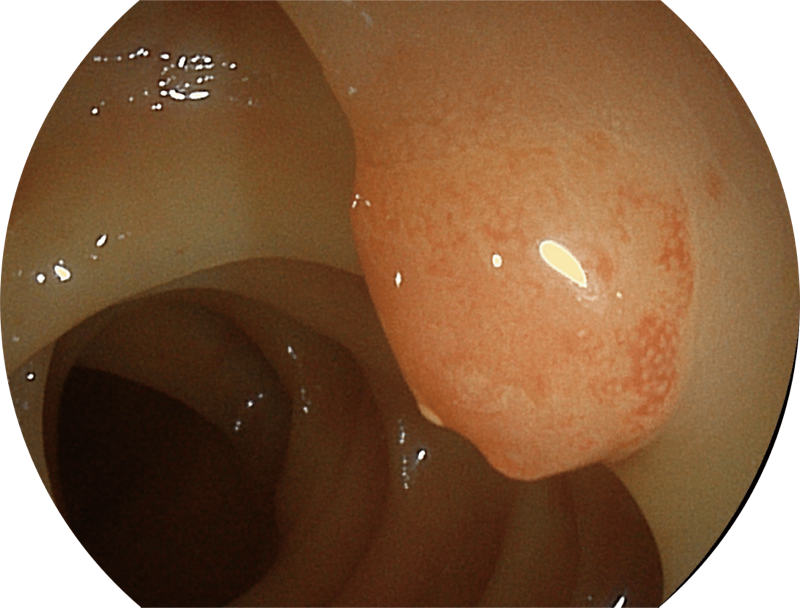

百万级像素高清传感器,1080P全高清视频信号输出,图像清晰。

弯曲角度大,方便观察食管下段贲门、胃底部等难以观察到的部位,减少盲区。

带来镜体插入及诊疗新体验。